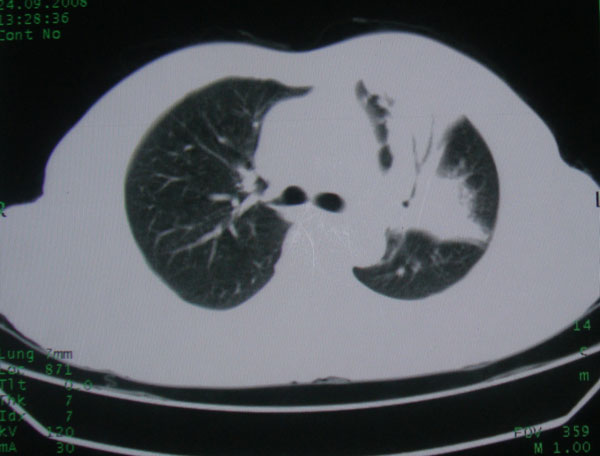

患者男性58岁因二周前起咳嗽,今天胸片示左上肺占位性病变行ct检查,无发热,无咯血痰.

左上肺感染性病变,结核伴空洞形成可能,左上肺膨胀不全

左肺上叶病灶,实变但见含气支气管、空洞但未见壁内结节及积液;

考虑:①感染性病变(包括特殊感染型肺tb)

②肿瘤性病变(考虑患者年龄比较大的关系/所以不排除)

初学者。。。左肺空洞性病变,并可见阻塞性肺不张改变,鉴于患者为老年男性,且临床症状仅有咳嗽,全身中毒症状不明显,所以我首先考虑为左肺癌性空洞并左侧肺门淋巴结转移伴左肺阻塞性肺不张。结核性空洞放于第二位考虑,可以进行相关实验室检查。希望能有病理结果,谢谢!!!!!

左肺上叶实变影,内见支气管充气征及空洞影,病人年龄较大,无发热及结核中毒症状,心影左移,未见纵隔淋巴结肿大;不知实验室检查结果如何?有否嗜酸细胞增多,有没有进行治疗?就目前资料首先考虑1.感染性病变,2.慢性嗜酸性肺炎?可结合实验室检查并短期治疗复查,肺癌不能排除。